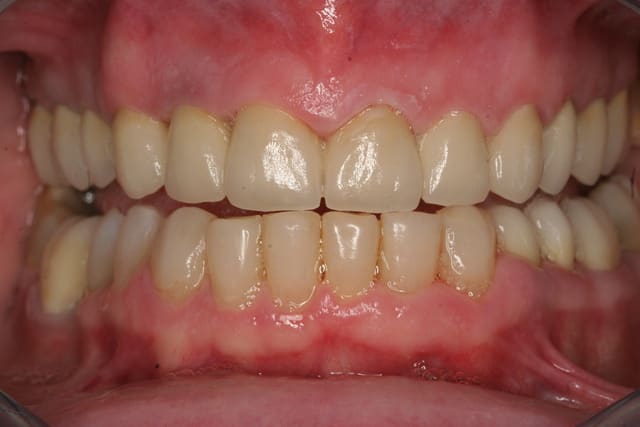

Et voila la pose , pour les habitants du nouveau monde c'est très coloré, pour les Franchouillard c'est naturel... perso je m'en fout la patiente est toute joilleuse et j'ai pas honte de moi, j'ferais encore mieux dés qu'on m'en donneras l'occasion.

Merci de m'avoir laisser finir sans me tailler un short tout de suite!

Fin 002 j3hb61 - Eugenol

Fin 005 htq1ba - Eugenol

Fin 006 dpgjbp - Eugenol

Fin 008 owjdyz - Eugenol

Fin 007 lhlszz - Eugenol